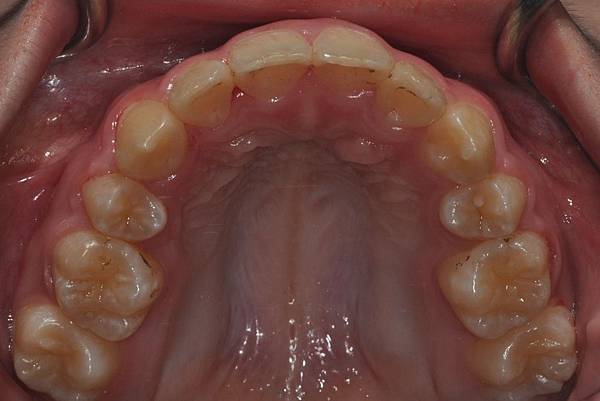

拔牙改善高位虎牙

虎牙妹的女神蛻變之旅~

此案例因為空間不足排列牙齒,

考量到不拔牙將使得牙齒前凸破壞患者原本和諧的側臉。

故上下左右各拔一小臼齒。